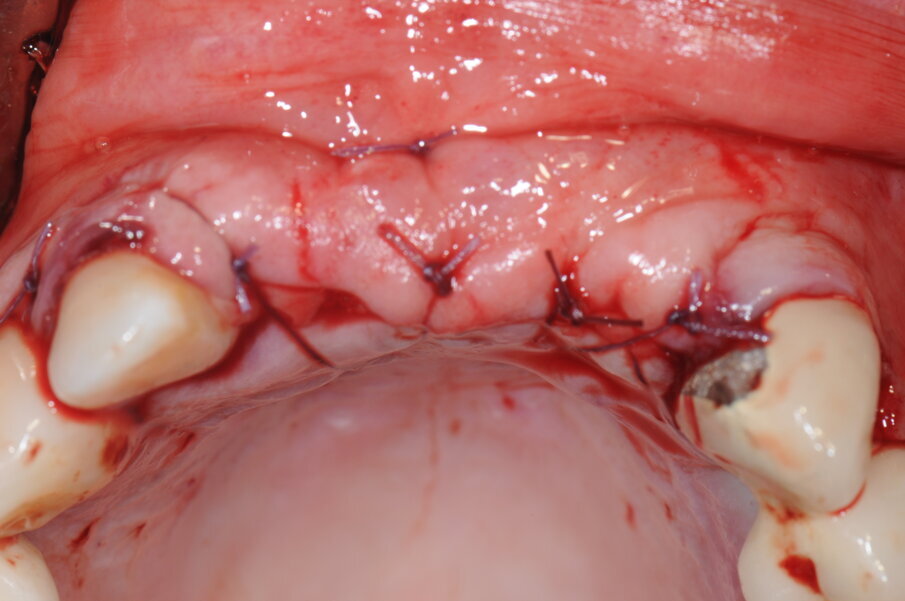

Il lembo, perfettamente passivo al di sopra del sito da rigenerare, è stato suturato con punti staccati auspicando una guarigione per prima intenzione (Figg. 8a, 12).

Fig. 12 - Sutura del lembo.